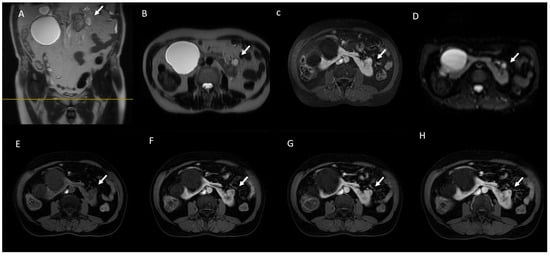

- The IIF type is a non-enhancing and heterogeneously hyperintense lesion with no contrast in the T1W image. This type of lesion is important because sometimes RCCs, especially papillary subtypes, are hemorrhagic and may show mild or absent enhancement [161].